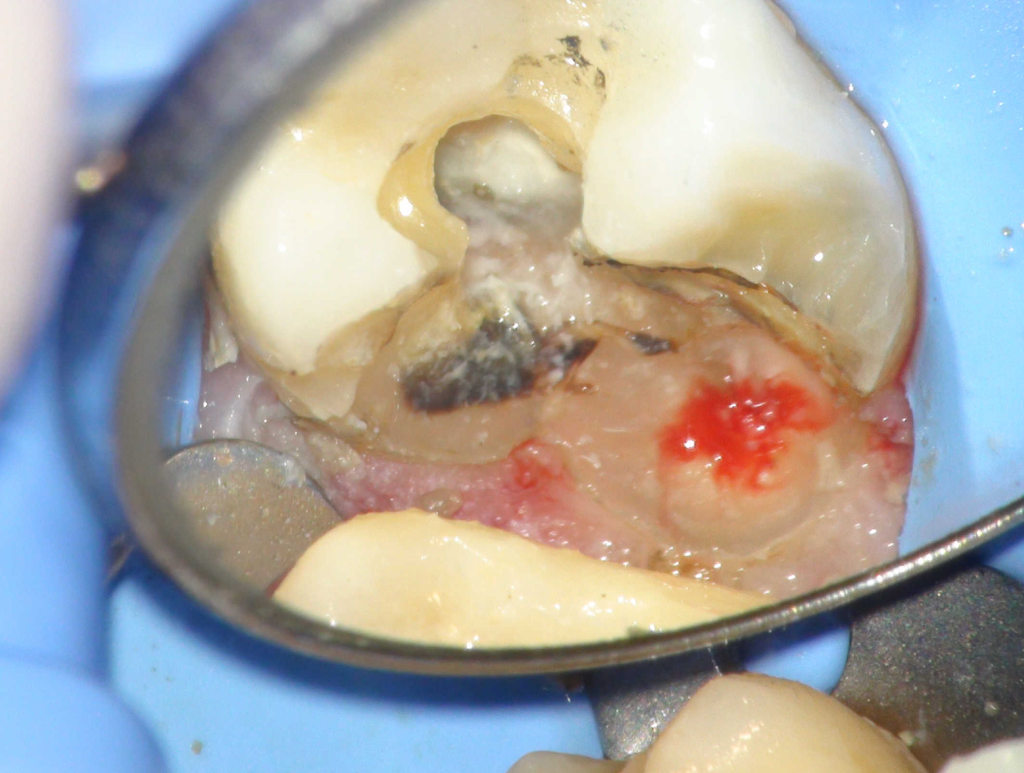

Fisura, remoción amalgama para explorar